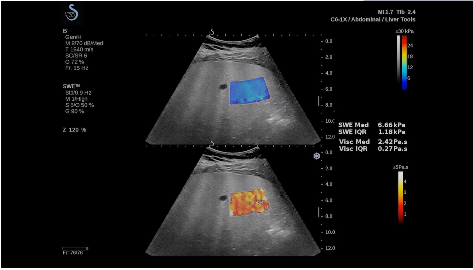

法國(guó)聲科影像(SuperSonic Imagine,SSI. Euroniex:FR0010526814)近日發(fā)表公告,宣布其研發(fā)的新一代“極速”超聲成像平臺(tái)(UltraFast Imaging),首次實(shí)現(xiàn)了肝臟的多項(xiàng)超聲定量評(píng)估新指標(biāo)同步檢測(cè),包括:Att PLUS,SSp PLUS和Vi PLUS等,基本涵蓋肝臟相關(guān)病理變化指征的如纖維化、脂肪變、炎癥等。據(jù)悉,此多項(xiàng)新技術(shù)新將搭載于新Aixplorer系列E超系統(tǒng)。

法國(guó)聲科影像公司(SuperSonic Imagine. SA,F(xiàn)rance),2005年由三位諾貝爾獎(jiǎng)級(jí)科學(xué)家主導(dǎo)創(chuàng)立,專注于E超的開發(fā)和生產(chǎn),是目前世界上唯一可以同時(shí)應(yīng)用兩種波進(jìn)行人體檢測(cè)的系統(tǒng):縱波形成高質(zhì)量的二維組織結(jié)構(gòu)圖像,而橫波可以使醫(yī)生實(shí)時(shí)準(zhǔn)確地看到并分析組織的硬度,有效減少有創(chuàng)檢查、避免損傷。

E超相關(guān)技術(shù)已被多項(xiàng)多中心大樣本研究證實(shí)對(duì)于肝纖維化無(wú)創(chuàng)評(píng)估有重要意義,同時(shí)也可全面應(yīng)用于乳腺、甲狀腺、肝臟、前列腺、肌骨、婦科等全身各組織器官的定量評(píng)估和鑒別診斷。在慢性肝臟方面,聲科E超的肝臟相關(guān)定量診斷技術(shù)集,于2018年獲得美國(guó)FDA認(rèn)證,成為FDA歷史上首次獲批的單病種超聲全面定量解決方案。